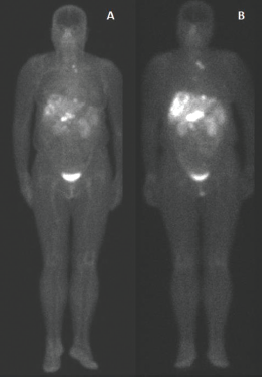

Figure 1. 99mTc-EDDA/HYNIC-TOC compared to 111In-DTPA-octreotide. Example of scintigraphy examination using (a): 111In-DTPA-octreotide and (b): 99mTc-EDDA/HYNIC-TOC in the same patient, showing a more significant number of foci of uptake using 99mTc.

In Figure 1, we have an example of the same patient evaluated by both imaging methods, showing a more significant number of foci of uptake with 99mTc-EDDA/HYNIC-TOC compared to 111In-DTPA-octreotide.